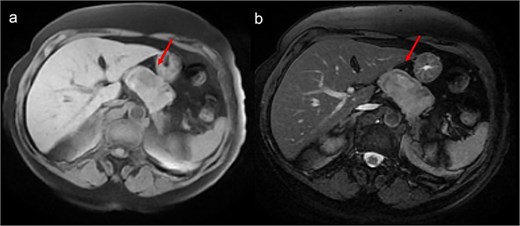

A thoraco-abdominopelvic computed tomography (CT) scan performed for staging revealed a well-defined, homogeneous soft-tissue mass anterior to the celiac trunk, superior to the pancreas, and medial to the stomach (Fig. 1). A positron emission tomography (PET) scan confirmed the previously known hypermetabolic retroareolar lesion of the right breast and revealed a large hypermetabolic mass in the celiac–mesenteric region, measuring 63 × 35 × 50 mm (Fig. 2). An abdominal MRI characterized the mass as a well-defined 6-cm lesion with mixed solid and cystic signal intensity, closely related to the celiac trunk, pancreas, stomach, and left adrenal gland (Fig. 3). Biochemical testing showed elevated urinary normetanephrine and metanephrine levels, consistent with catecholamine hypersecretion.

Abdominal MRI showing a heterogeneous intermediate T1 signal mass (a) with slight hyperintensity on T2-weighted images (b), without fatty components, closely contacting the stomach but distant from the liver.